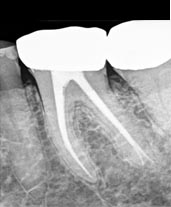

La endodoncia, también conocida como tratamiento de conductos, es el procedimiento que utilizan los odontólogos para eliminar -en parte o en su totalidad- la pulpa del diente y sellar el conducto pulpar. La pulpa es la parte más interior del diente y está constituida por un tejido blando que contiene los nervios y los vasos sanguíneos. La parte del conducto que se encuentra en el interior de la corona se denomina cavidad pulpar, mientras la correspondiente a la raíz recibe el nombre de conducto reticular y es el que conecta con el hueso maxilar.

La causa más frecuente de la infección y consecuente inflamación y necrosis de la pulpa, y por tanto de la necesidad de realizar una endodoncia, es la existencia de caries, aunque existen otros factores que pueden generar una pulpitis o lesión de la pulpa: